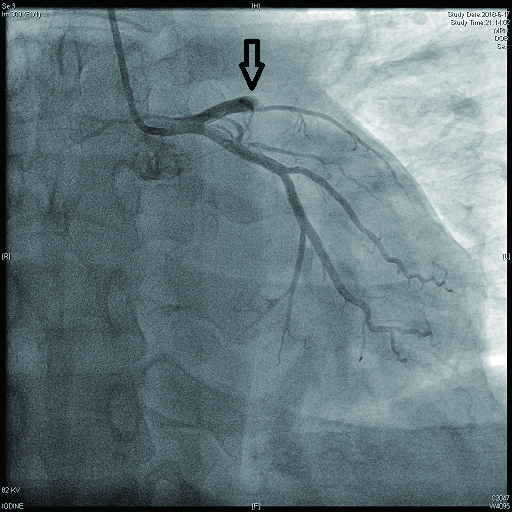

病例1 1 LAD近段(图 9 75%~90% 2级 LAD近段植入支架1枚

病例2 3(图 6~8 LAD近段 次全闭塞 2级 LAD近段植入支架1枚

病例3 1 LAD中段 闭塞 0级 LAD中段植入支架1枚

病例4 3 LAD中段及D1(图 11 LAD 85%及D1闭塞 0级 LAD中段植入支架1枚

病例5 1 LAD中段 闭塞 0级 LAD中段植入支架1枚

病例6 1 LAD中段(图 10 闭塞 0级 LAD中段植入支架1枚

病例7 1 LAD近段 次全闭塞 2级 LAD近段植入支架1枚

图 6 病例2冠脉造影示LAD中段病变

图 7 病例2冠脉造影示LCX病变

图 8 病例2冠脉造影示RCA病变

图 9 病例1冠脉造影示LAD近段病变

图 10 病例6冠脉造影示LAD中段闭塞

图 11 病例4冠脉造影示LAD狭窄,D1闭塞